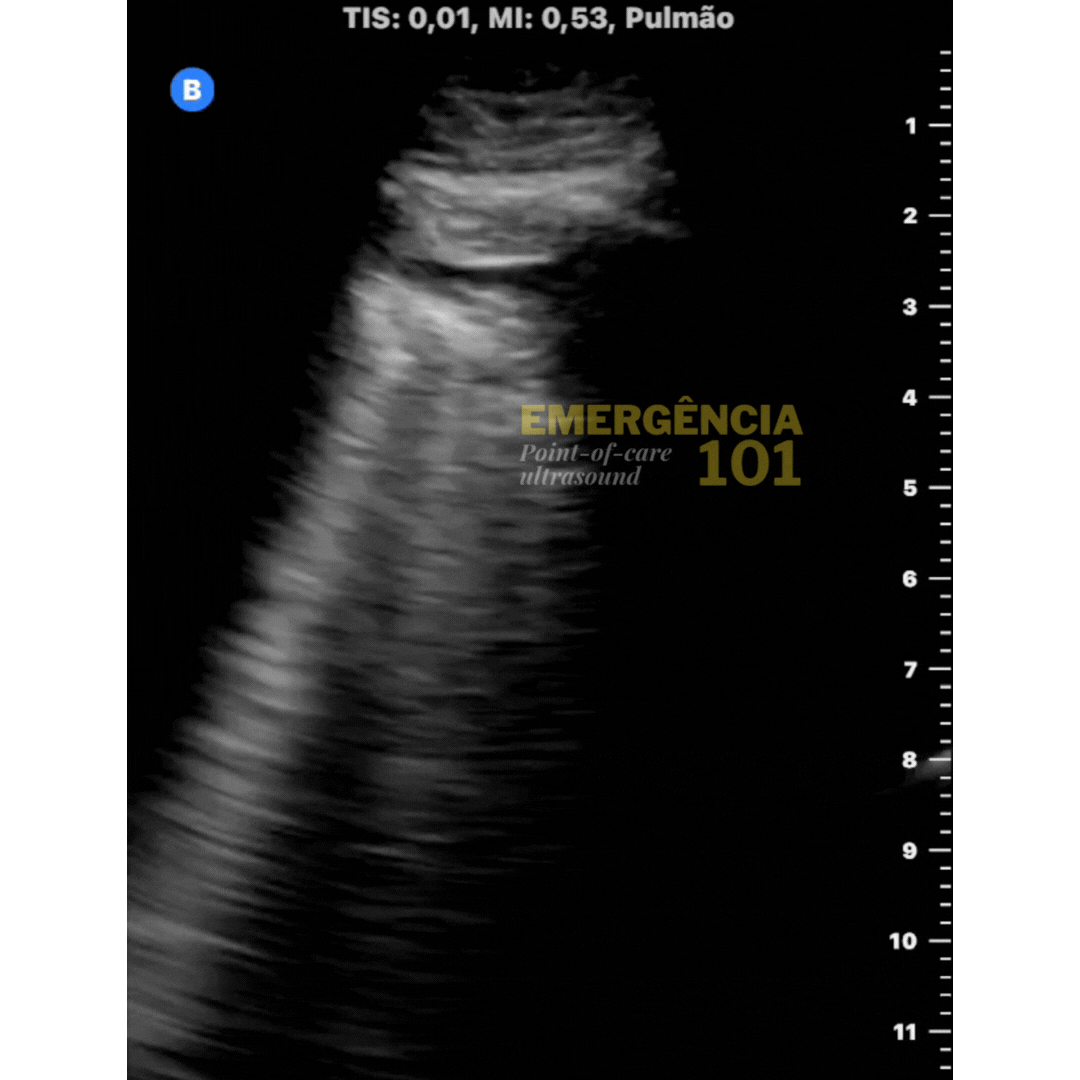

Figura 7a. Lung-point em paciente intubado e internado no hospital por hemorragia digestiva alta, evoluindo com aumento da necessidade de O2. Diagnóstico: pneumotórax (barotrauma?) Acervo pessoal do autor.